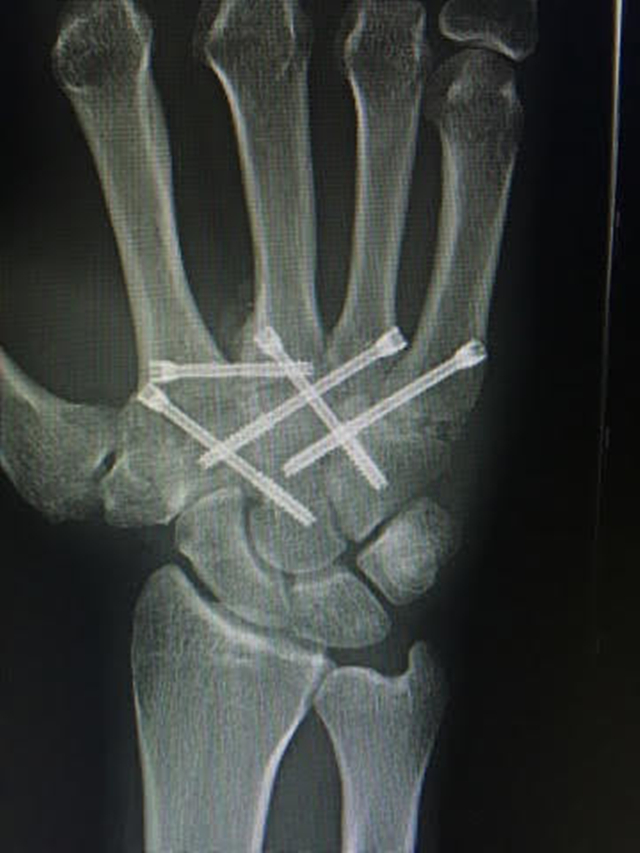

下图是他手掌的X光,显示着里面放着很多钢钉。从这可见有时候拳击选手的一拳,力量真的非常大,因为在拳击赛场上一拳把自己手打废,打伤的有很多,甚至还有被连续重拳打死的,还有一些身体器官被损坏的,就像下面这位,